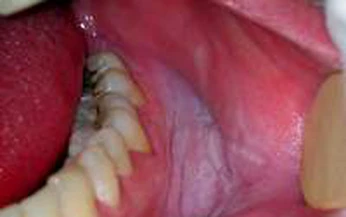

Tra cứu bệnh 16/10/2024 18:54SKĐS - Bệnh bạch sản là bệnh lý gây ra những mảng da dày, trắng trên lưỡi và trong lớp lót niêm mạc miệng. Bệnh thường không gây hại và có thể tự biến mất. Tuy nhiên, trong các trường hợp nghiêm trọng có thể dẫn tới ung thư miệng.

Tra cứu bệnh 30/07/2024 05:44SKĐS - Bạch sản là tình trạng xuất hiện những mảng dày màu trắng trong khoang miệng. Mảng trắng này do sự tăng trưởng quá mức của các tế bào. Điều trị bệnh bạch sản hiệu quả nhất là khi bệnh được phát hiện sớm, khi các mảng bạch sản còn nhỏ.